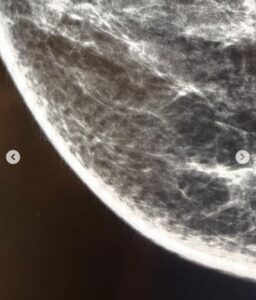

“Fiz minha primeira mamografia – exame de imagem mais eficiente para diagnóstico precoce de #cancerdemama Foi tudo bem! E teria sido trivial senão fosse a terceira vez que eu estava tentando… Das outras duas vezes senti muita dor enquanto me posicionavam na máquina, fiquei assustada. Disseram que a “minha sensibilidade” poderia ser pela proximidade do período menstrual ou pelo tamanho pequeno da minha mama… Achei que não suportaria aguardar o click das 4 imagens, desisti.”

A jornalista destacou as barreiras que enfrentou em suas tentativas anteriores, descrevendo a dor intensa e o desconforto que a impediram de concluir o exame. No entanto, a terceira tentativa foi marcada por uma determinação renovada, uma atitude resiliente e um claro entendimento da importância vital do procedimento.

“Das outras duas vezes senti muita dor enquanto me posicionavam na máquina, fiquei assustada. Disseram que a ‘minha sensibilidade’ poderia ser pela proximidade do período menstrual ou pelo tamanho pequeno da minha mama… Achei que não suportaria aguardar o click das 4 imagens, desisti”, compartilhou Millena em sua postagem.